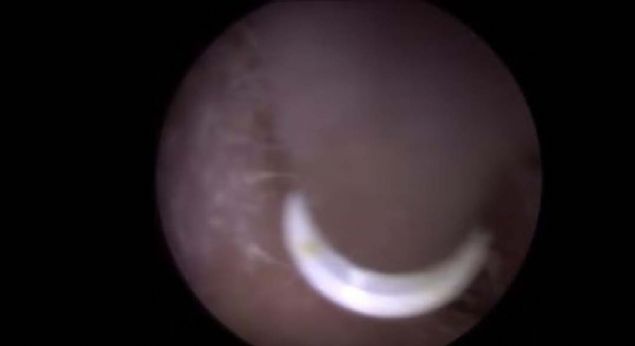

Kolundaki yaranın içinden çıkanlara kimse inanamadı!

Kolunda yara çıkan genç kadın sivilce zannedip önemsemedi ancak gerçek doktora gidince ortaya çıktı.

Yaranın içinden çıkan tropikal bölgede yaşayan ve larvalarını deri altına bırakan botfly cinsi sinekti.

Kolunda yara çıkan genç kadın sivilce zannedip önemsemedi ancak gerçek doktora gidince ortaya çıktı.

İşte o anlar...